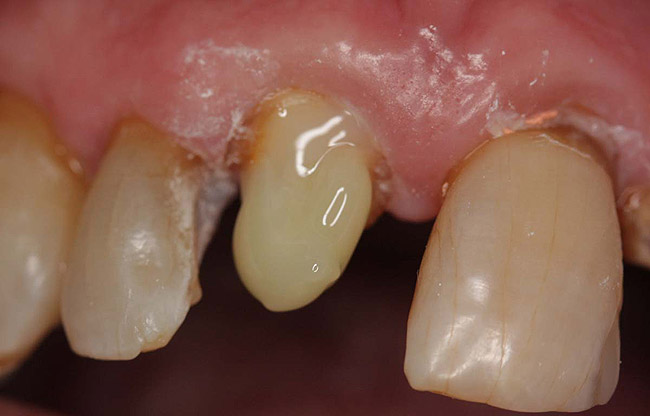

A Class IIIN maxillary left second molar required restoration (Figure 6). Four canals, a chamber space, and little cross section of tooth structure were in the gingival third. Gutta-percha was removed with a Peeso reamer supplied in the C-1 kit. The canal was shaped with a bur in the kit, which was the same size as the corresponding post (Figure 7). The tooth structure was bonded with Brush & Bond™ (Parkell, www.parkell.com), and then the resin cement was spun into the canal with a lenticulo spiral. A C-1 white post was placed in the palatal canals (Figure 8). The C-1 White Post is a fiber-reinforced composite post, which flexes at the same rate as dentin to minimize root stresses.

Core build-up was completed with Absolute Dentin™ (Parkell, www.parkell.com) dual-cure high-strength core composite. There are variations on color and how materials cure. For example, Light-Core™ (Bisco, www.bisco.com) is a light-cured blue material, Encore® (Centrix, www.centrixdental.com) is a self-cure white material, and Para Core (Coltène Whaledent, www.coltene.com) is a dual-cure white or dentin-colored material. Material was placed directly and light-cured for 40 seconds (Figure 9). Final preparation for a PFM was completed (Figure 10). The final crown was placed (Figure 11).

Figure 10  Final tooth preparation to accept a PFM crown.

Figure 10

Figure 11  Final porcelain-fused-to-metal crown.

Figure 11